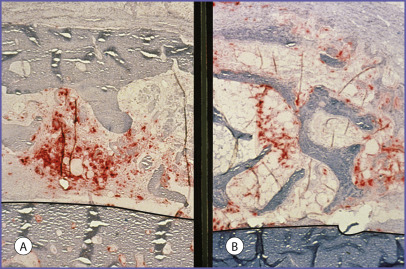

Lin evaluated the volume persistence of calvarial and iliac crest grafts fixed to the rabbit snout with lag screws ( Fig. 3.1 ). Early revascularization of the grafts occurred only in the cancellous portion of both grafts suggesting that the cortical portion of the grafts acted as a mechanical barrier to ingrowing blood vessels ( Fig. 3.2 ). This observation prompted Chen’s study.

Using a model similar to Lin’s, Chen et al. also evaluated the volume persistence of calvarial and iliac crest grafts fixed to the rabbit snout with lag screws. In addition, Chen correlated graft revascularization and graft resorption with graft architecture in the cortical and cancellous regions of both calvarial and iliac grafts. Revascularization was evaluated using latex vascular cast injection, while osteoclastic activity was evaluated using a tartrate-resistant acid phosphatase stain. As expected, he found that at 70 days the calvarial grafts demonstrated greater volume maintenance than the iliac bone (72% vs. 32%, P < .025). He found significantly greater revascularization and osteoclastic activity in the cancellous portion of both the calvarial and iliac crest bone grafts by the 10th day after onlay grafting. Minimal activities were present in the cortical bone ( Figs. 3.3 and 3.4 ). Because calvarial grafts contain more cortical bone, the superior volume maintenance can be understood by the influence of bone architecture on revascularization and resorption. Cortical bone is more slowly revascularized, and therefore less available to osteoclastic activity. The amount of cortical bone in an onlay graft determines its volume maintenance. The importance of graft architecture, as opposed to its embryologic origin, to the volume persistence of onlay bone grafts has been supported in later studies by Gosain.